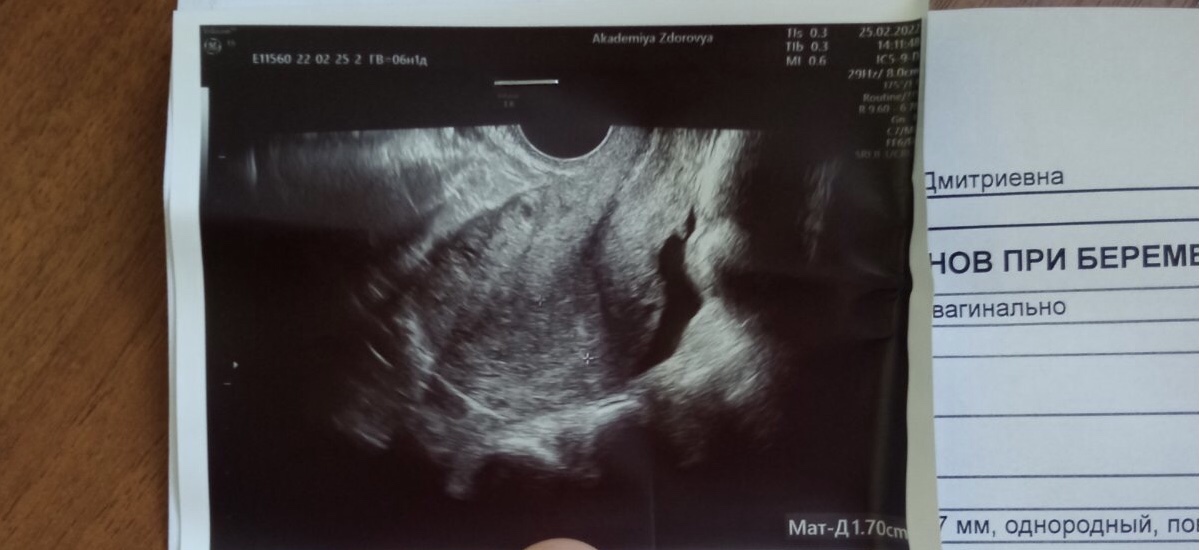

Всем привет. Девочки помогите пожалуйста🙏 К врачу только в начале марта. В общем тесты положительные, по месячным срок 6 недель и 2 дня. Вчера решила для себя сходить на узи, посмотреть есть ли плодное яйцо. Но там его не видно. Сказали, что возможно срок меньше. И отправили на хгч. Вчера же сдала хгч, результат 431, по нормам клиники это 2 неделя вроде. Сказали повторно на уз придти через неделю, но а если всего 2 недели срок то там тоже не покажет плодное. Очень переживаю, у кого так же было??? Фото прикреплю)

А ещё вот это включение очень похоже на пя, маленькое, оно тоже имеет ободок, но я не уверенна...